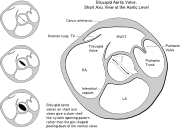

| 18:29, 9 October 2012 | Heart bicuspid aortic valve.svg (file) |  |

28 KB | Description: Heart bicuspid aortic valve anatomy Date: 23 December 2006 Author: Patrick J. Lynch, medical illustrator Creative Commons Attribution 2.5 License 2006 | 1 |